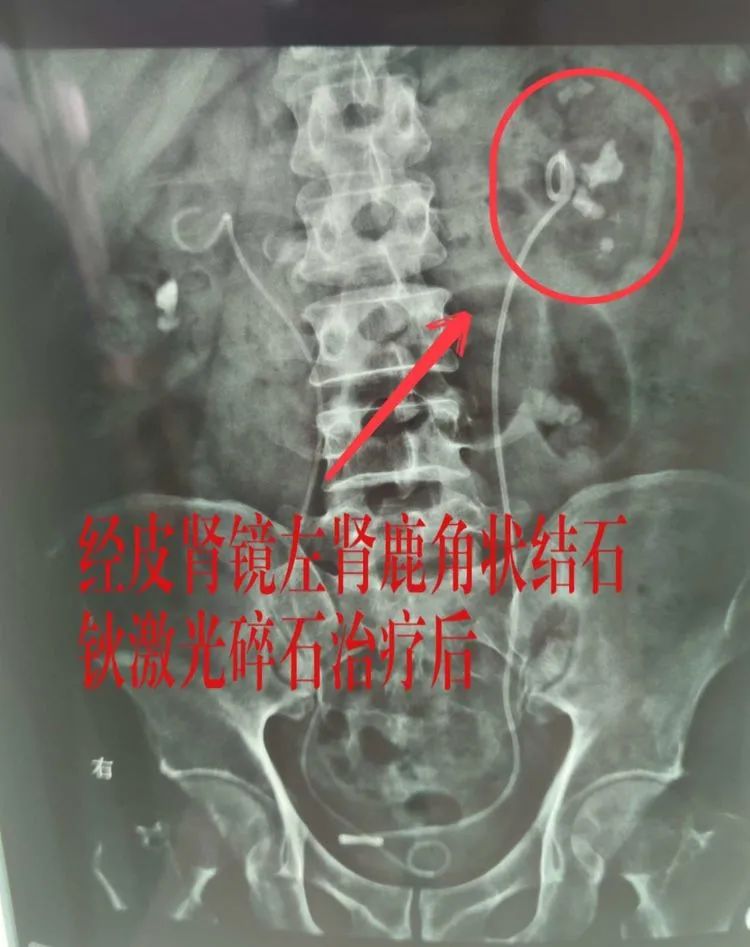

以经皮肾镜钬激光碎石治疗左肾结石为例,体外碎石的排石等待时间较长,而开放式手术创伤大,比较之下钬激光碎石创伤小、恢复快,就具有明显的优势。还有输尿管硬镜、软镜等多种微创诊疗方式,都可以让患者的结石无所遁形。